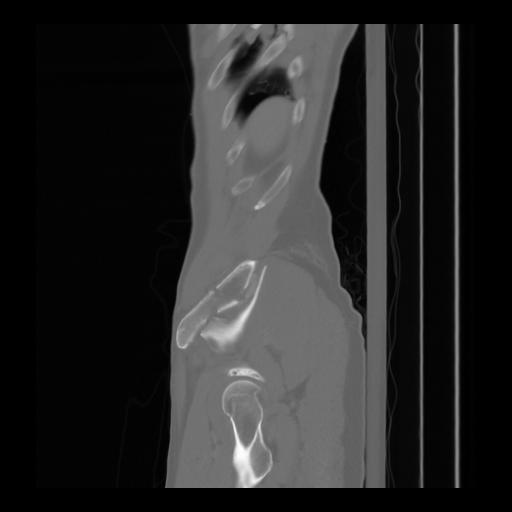

36 CUERPO,CE,Sagittal,3.000,CUERPO,Sagittal,